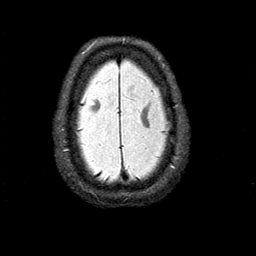

Alzheimer's disease MR T2-weighted -- Slice #43

[Home][Help][Clinical][Tour 1][Tour 2] Slice 43